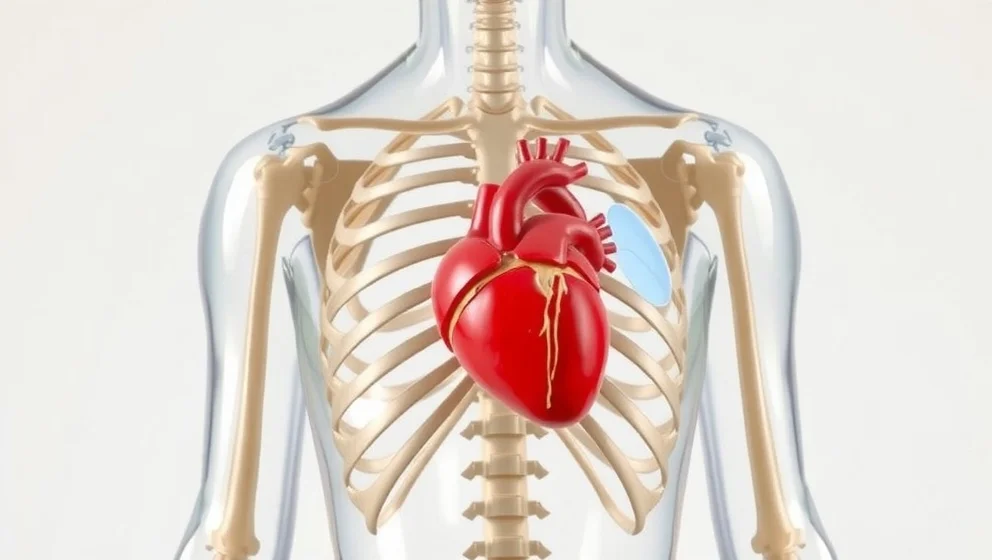

Hjärtat ligger i bröstet, lite till vänster om mitten. Du lär dig var det sitter, hur stort det är och vad det gör varje dag.

Hjärtat sitter inte i mitten av bröstet som många tror. Det ligger faktiskt lite åt vänster och är ungefär så stort som din knytnäve.